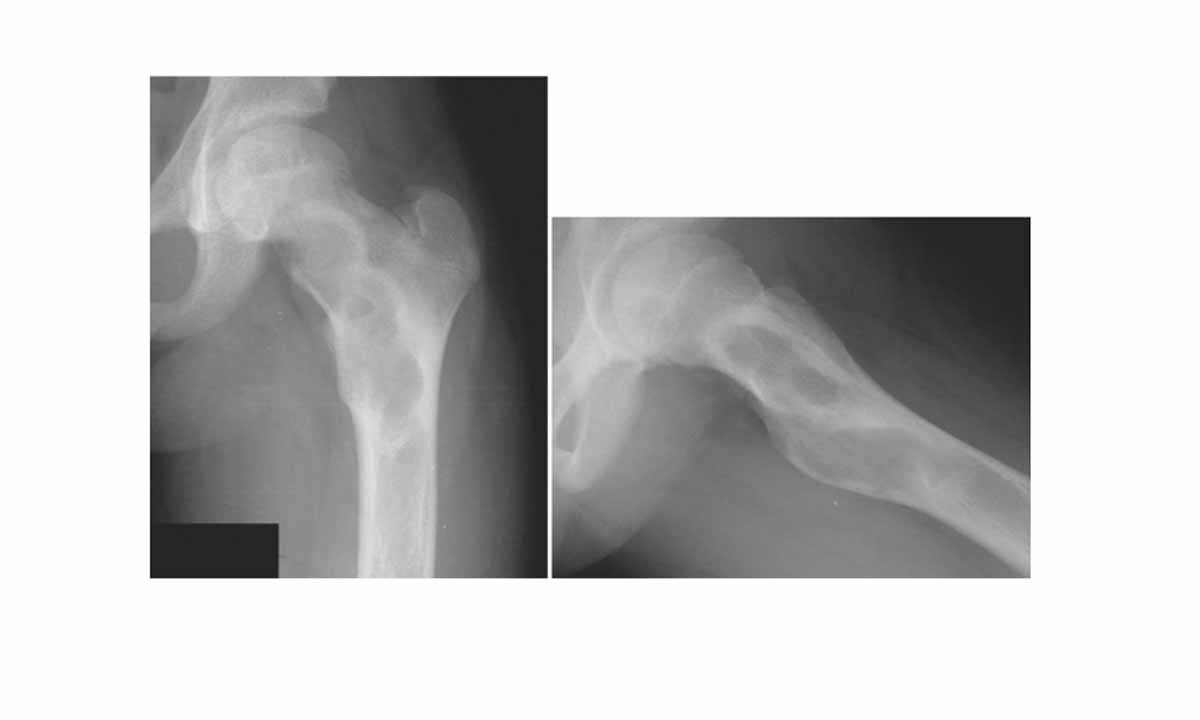

Fibröz displazinin varlığı, kemik röntgenleri ve biyopsi yapılarak kemik dokusundan alınan örneğin laboratuvarda incelenmesi ile doğrulanır.